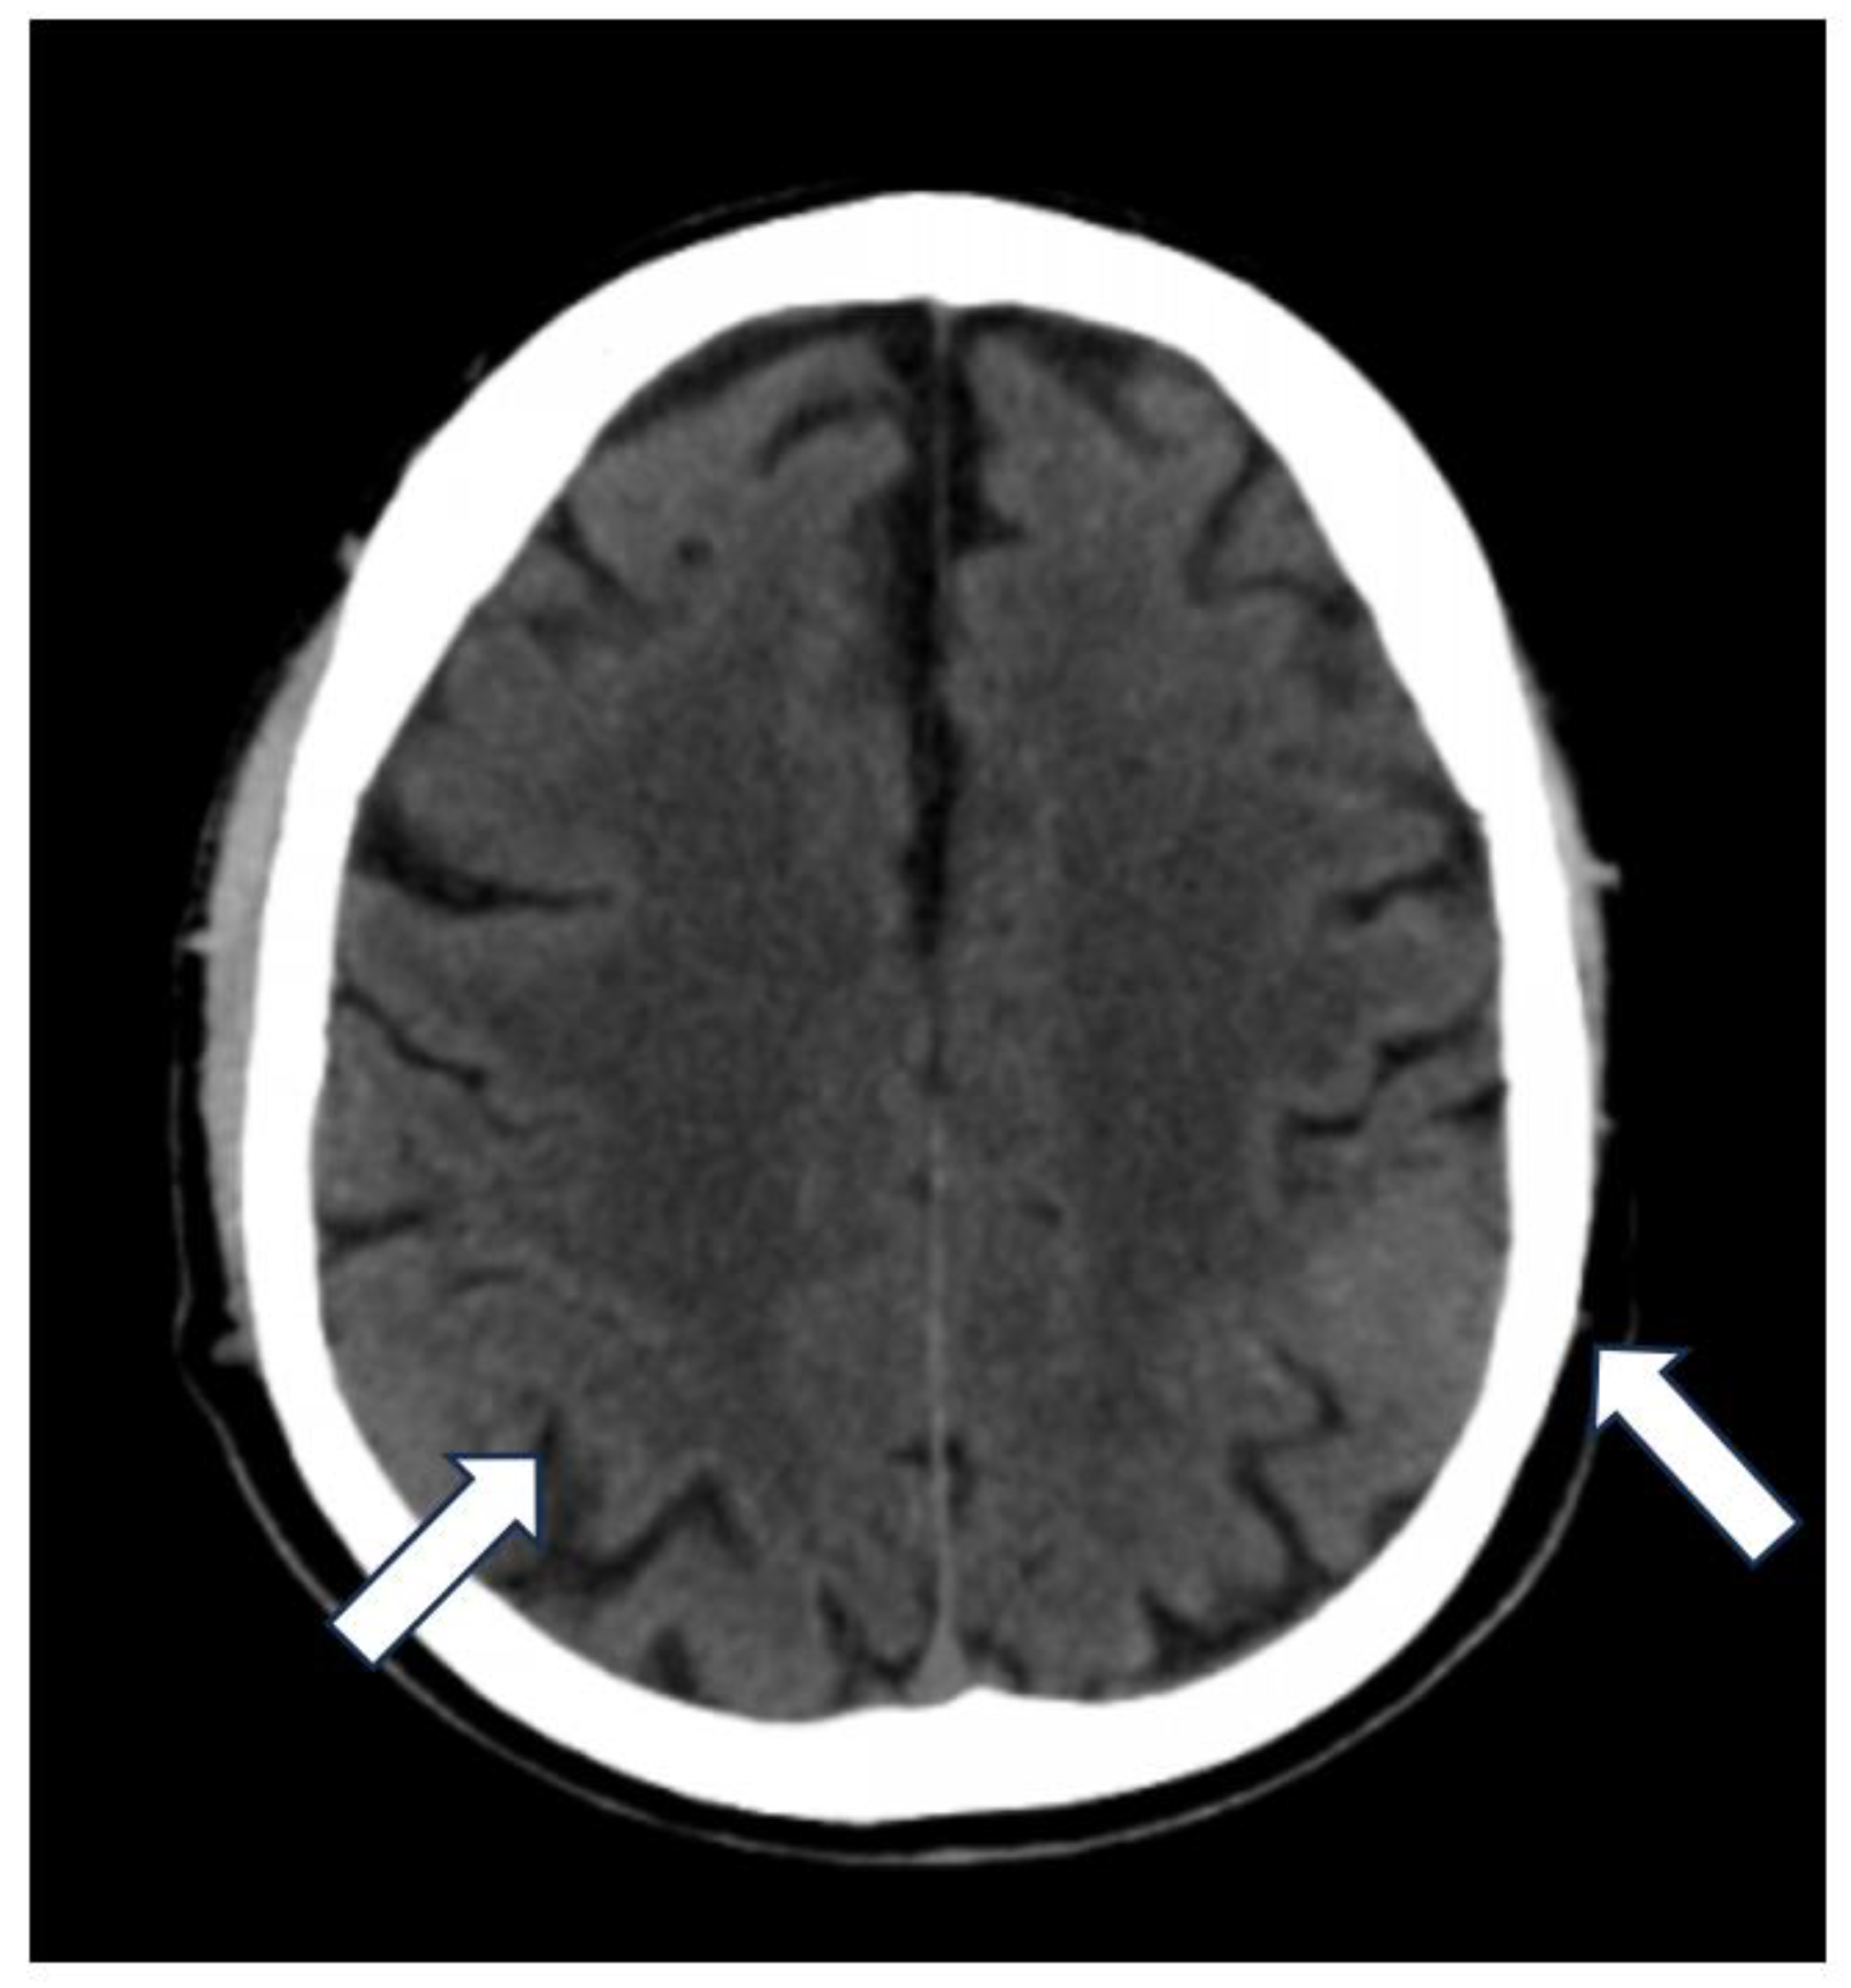

Figure 1.

The unenhanced CT axial image reveals on the left side the disappearance of the physiological hypodensity of the subarachnoid spaces in parietal region where, instead, there is a slight hyperdensity (arrows).